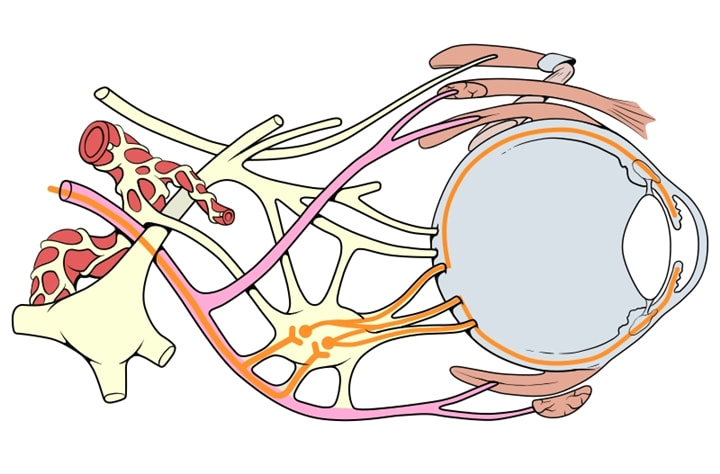

Is any tumor that occurs within the orbit of the eye. The orbit is a bony housing in the skull about 2 inches deep that provides protection to the entire eyeball except the front surface. It is lined by the orbital bones and contains the eyeball, its muscles, blood supply, nerve supply, and fat.

Tumors might develop in any of the tissues surrounding the eyeball and might also invade the orbit from the sinuses, brain, or nasal cavity, or it might metastasize (spread) from other areas of the body. Orbital tumors can affect adults and children. Fortunately, most are benign.